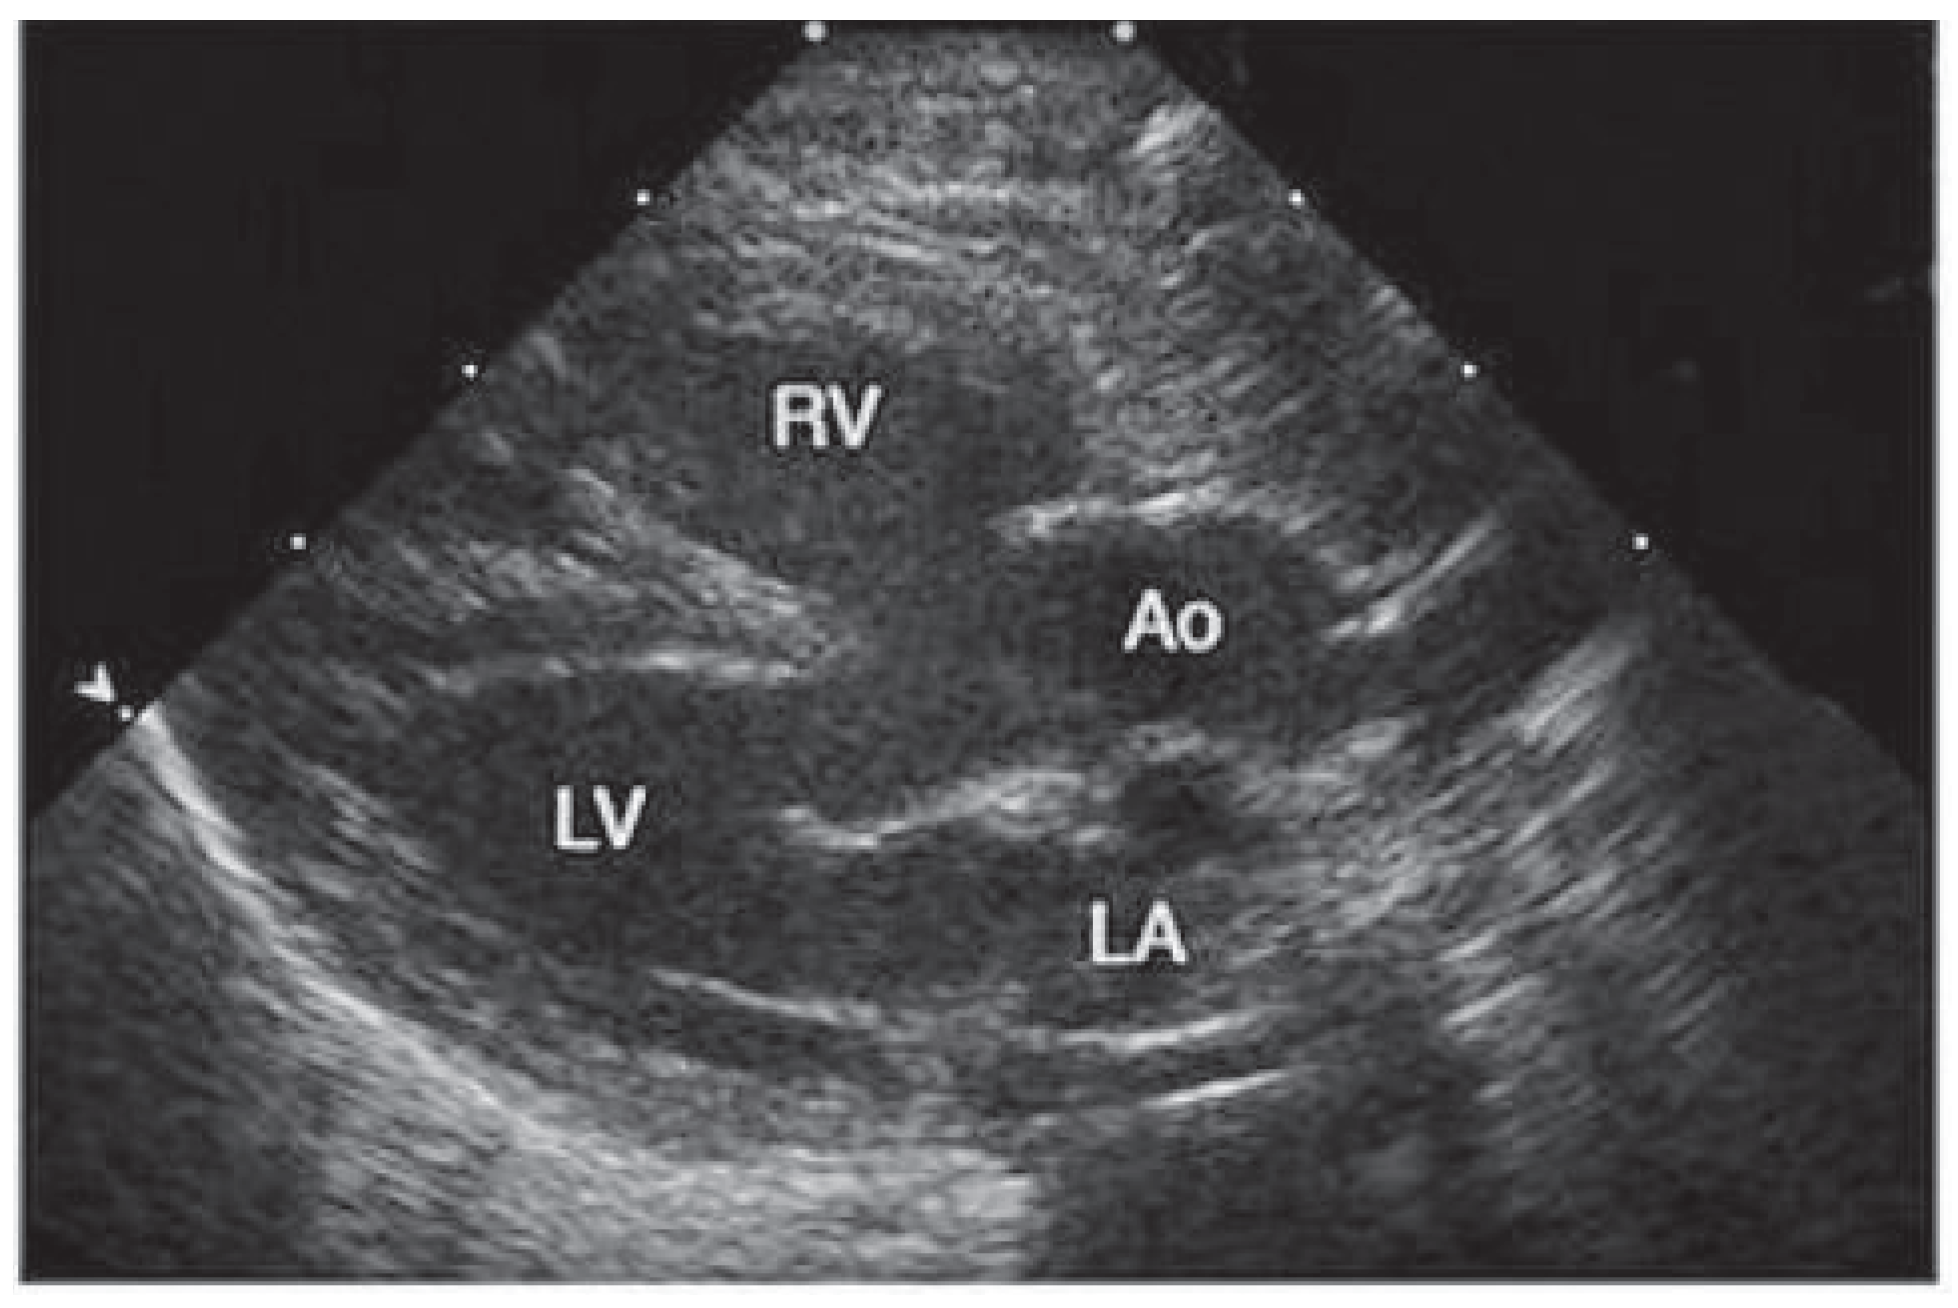

Tetralogy of Fallot, first described by Etienne Fallot [1] (Figure 1) in the classic paper “l’anatomie pathologique de la maladie bleue” in 1888, is the most common cyanotic congenital heart defect (6%). It compromises an interventricular septal defect, right ventricular outflow tract obstruction, an overriding aorta, and a right ventricular hypertrophy (Figure 2 and Figure 3).

Figure 3. Echocardiogram with anterior displacement of the outflow ventricular septum that results in stenosis of the subpulmonic right ventricular outflow tract, overriding of the aorta, and an associated ventricular septal defect. (This picture was published in: Nelson Textbook of Pediatrics. Kliegman RM, Behrman RE, Jenson HB, Stanton BF, edts. 18th edition. Oxford: W. B. Saunders; 2007. Copyright © 2009 Elsevier, Oxford, UK.) Ao = overriding aorta; LA = left atrium; LV = left ventricle; RV = right ventricle.